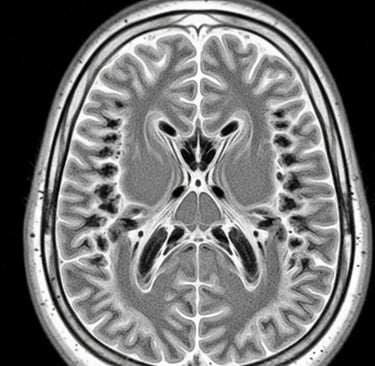

Ressonância Magnética (RM) do cérebro com achados típicos na substância branca; 2) Teste genético para confirmar duas alterações no mesmo gene EIF2B. Se a RM “bate” com VWM e só aparece uma alteração, o time médico precisa procurar a segunda; se nenhuma é encontrada, é preciso buscar outra causa. Por vezes, centros de referência em leucodistrofias ajudam a interpretar exames de imagem e genética.